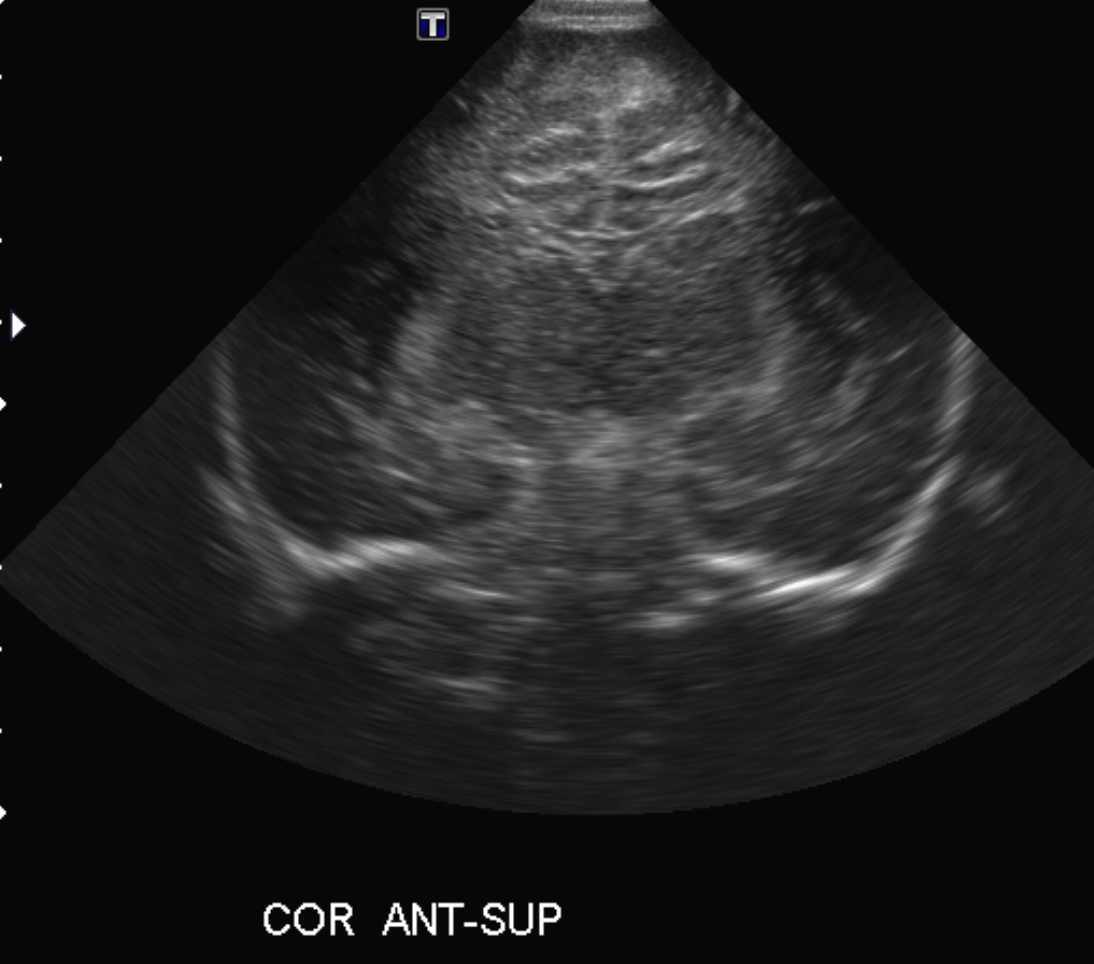

Neonatal Head Ultrasound

Findings

Brain

CSF spaces/ventricular system